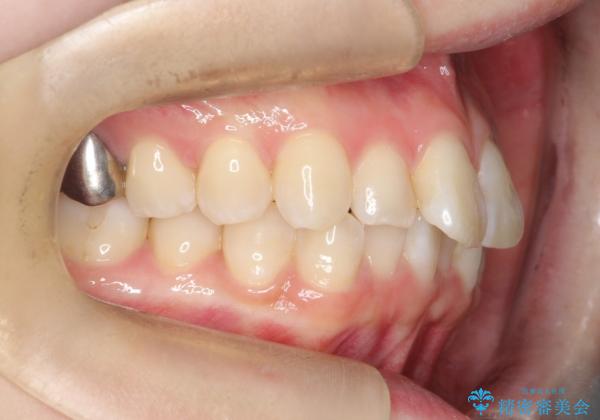

前歯のガタつきをマウスピース矯正で改善

- 前歯のガタツキが気になると来院されました。

奥歯の噛み合わせは綺麗に噛んでいたため、前歯の叢生(でこぼこ)に集中して治療するように計画しました。